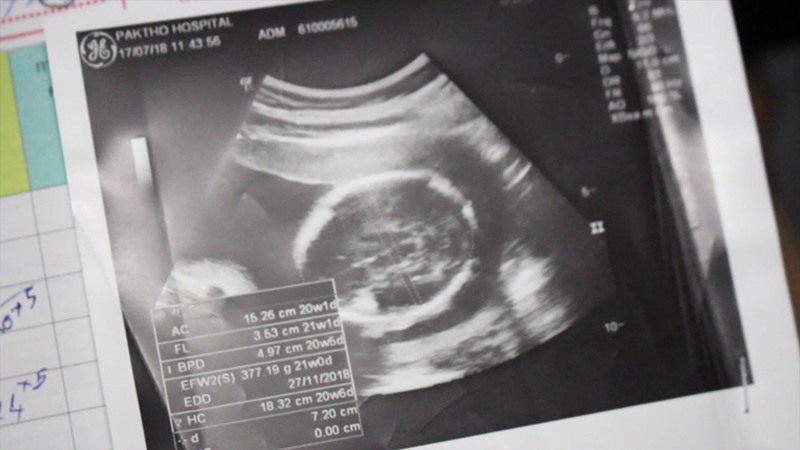

วันที่ 6 ธันวาคม 2561 Workpoint News รายงานว่า น.ส.ปริชาติ บัวทอง อายุ 41 ปี และนายวิเชียร ปานดาทอง อายุ 34 ปี สองสามีภรรยา ชาว ต.ทุ่งหลวง อ.ปากท่อ จ.ราชบุรี เข้าร้องเรียนสื่อมวลชน ขอความเป็นธรรมให้ ด.ช.อภิวัฒน์ ปานดาทอง ลูกชายอายุครรภ์ 9 เดือน ที่เสียชีวิตจากรกพันคอในครรภ์ แม้แพทย์จะระบุว่า เป็นเหตุสุดวิสัย แต่ทางครอบครัวก็มองว่า การสูญเสียที่เกิดขึ้นในครั้งนี้เกิดจากความสะเพร่าของพยาบาลของโรงพยาบาลประจำ อ.ปากท่อ ที่ไม่สนใจผู้ป่วยเท่าที่ควร

จากนั้น เวลา 05.00 น. พยาบาลคนดังกล่าวได้เดินเข้ามาตรวจดู ปรากฏว่าเด็กไม่หายใจจึงรีบตามหมอเข้ามาดู เมื่อหมอเข้ามาและอัลตราซาวด์ครรภ์ดูพบว่า เด็กไม่หายใจแล้ว ก่อนจะตามพ่อของเด็กเข้ามา และได้แจ้งว่ารกพันคอเด็กเสียชีวิตในครรภ์